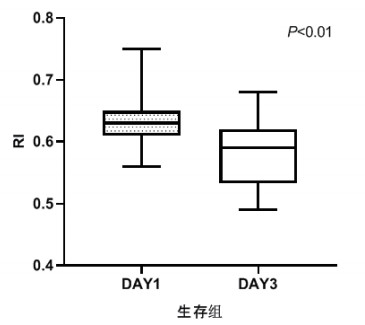

TCD参数组内治疗前后比较,生存组中无论PI还是RI在第3天时均较第1天有了明显下降,具有统计学意义(P < 0.05), 见图 2和图 3。死亡组在第1天和第3天测得的PI和RI值比较差异无统计学意义(P > 0.05),见图 4和图 5。可见生存组经治疗后脑循环较前改善,而死亡组治疗前后脑循环无明显改变。

| 图 3 生存组第1天和第3天RI比较 Fig 3 Comparison of RI between the first day and the third day in the survival group |